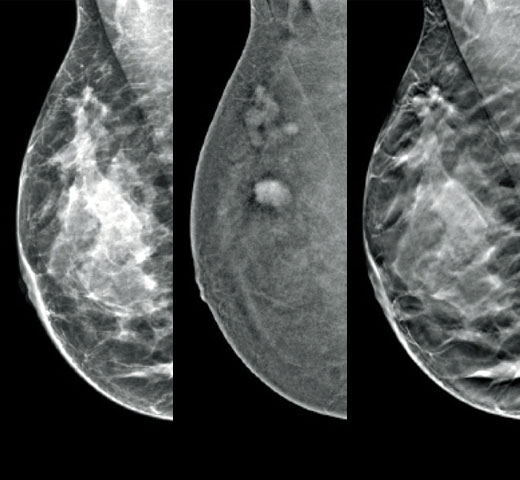

Higher breast density is known to increase a woman’s risk for breast cancer.1 The need for accurate, unbiased analysis is therefore critical. Powered by machine learning, Quantra technology software analyses both 2D™ and tomosynthesis images for distribution and texture of parenchymal tissue. It categorises breasts in four breast composition categories consistent with guidance from the American College of Radiology (ACR) BI-RADS Atlas 5th Edition.2

In addition to volume, pattern and texture of fibroglandular tissue may play just as an important role in mammographic cancer risk prediction.3-5 By analysing and categorising breast texture and pattern, our technology can deliver the accurate information you need to achieve more consistent and reliable scoring and confidently design patient-specific screening.

Objective machine learning algorithm that assigns breast density category based on analysis of breast tissue texture and patterns.